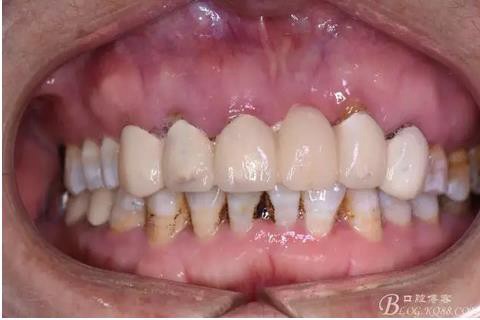

圖2.拆冠、重新根管治療11和12.

圖3.術(shù)前口內(nèi)正面照:12前庭溝輕度捫痛、有乒乓感